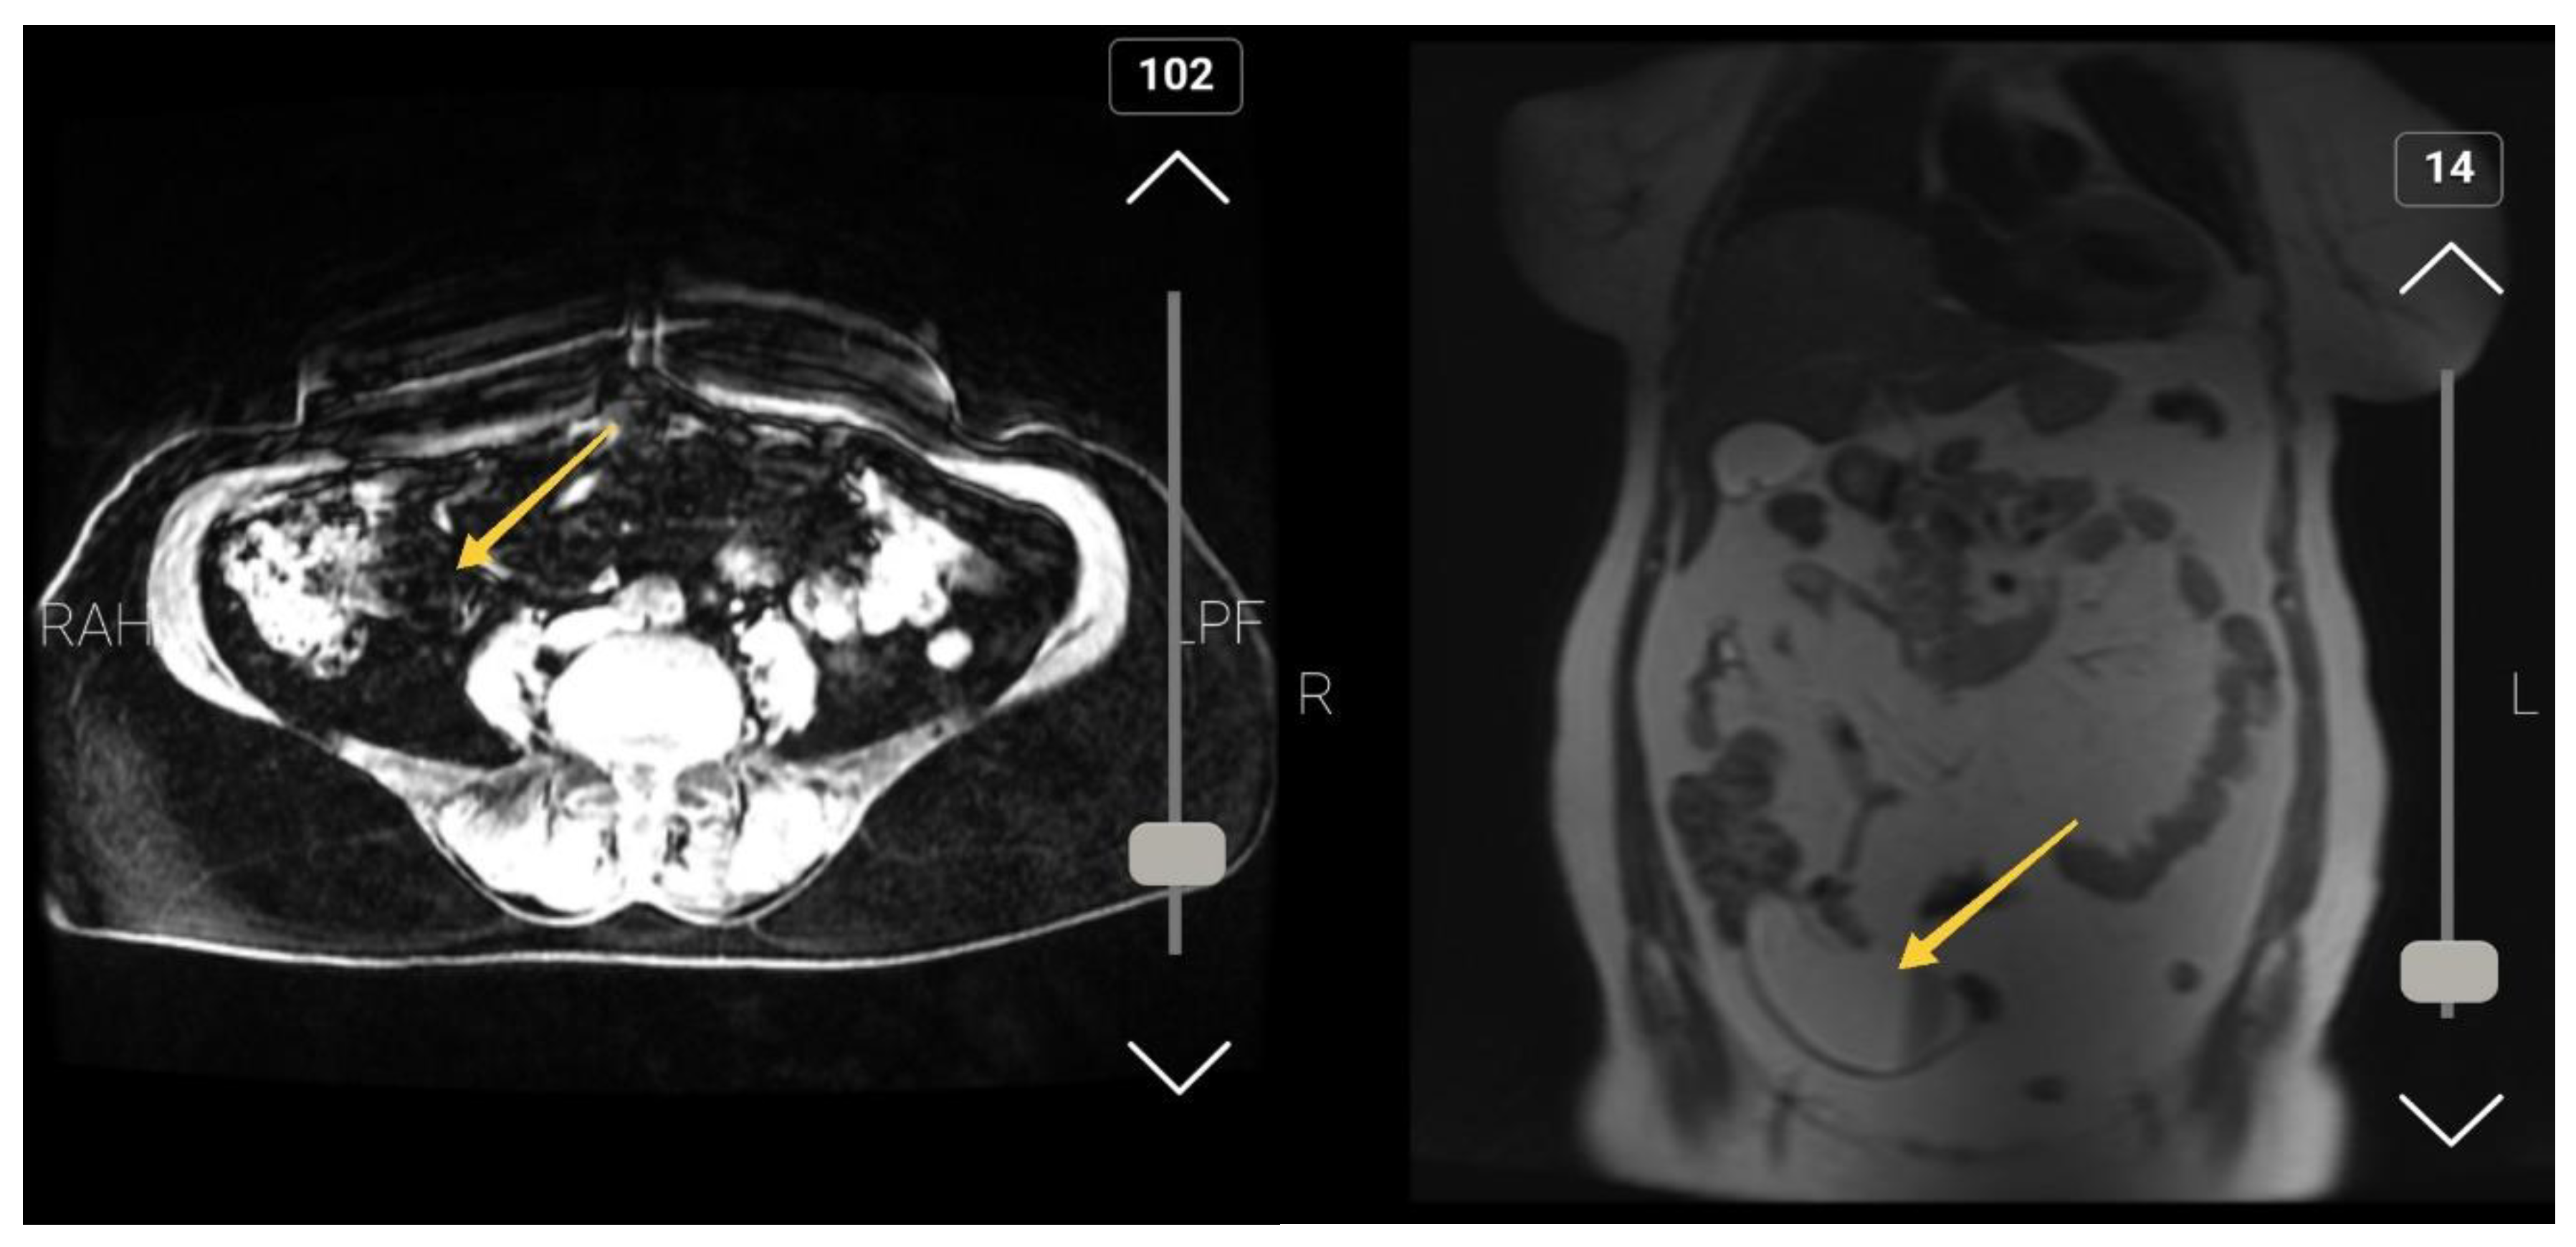

A 60-year-old female with a seven-month history of right lower quadrant pain aggravate in the last two weeks presented to the surgery emergency department of Golestan Hospital of Ahwaz. The patient mentioned weakness, fatigue, and decreased appetite from three month ago but didn't say any history of nausea, vomiting, or weight loss. She was afebrile at admission. The past medical history, past surgical history, family history, drug history and habitual history were negative. A physical exam showed tenderness and rebound tenderness in the RLQ (McBurney’s point), but Rovsing's sign was negative. other clinical examinations were normal. The patient’s WBC count was 13400 (Neutrophil=82 %), Hemoglobin= 12.3, and had normal urine analysis. In her medical records (Abdomen CT-Scan with and without IV contrast), fluid signal tubular mass measured 105 * 37 mm in RLQ is noted suggested for mucocele appendicitis (Figure 1). After admission, she became NPO (Nothing by Mouth), and after antibiotic therapy (Ceftriaxone and metronidazole IV) and hydration (1/3, 2/3 1/3-2/3 intravenous fluid) and pack cell reservation she candidate for surgical management. Appendectomy was performed through McBurney incision and the base of the appendix was free, no lymphadenopathy was seen (Figure 2).

On imaging findings for the neoplastic process, we expect round-encapsulated cystic mass with irregular walls and soft tissue thickening that is similar to our study that tubular mass measured 105 * 37 mm.

Figure 1. Sagittal and Coronal view of the abdomen CT-Scan.